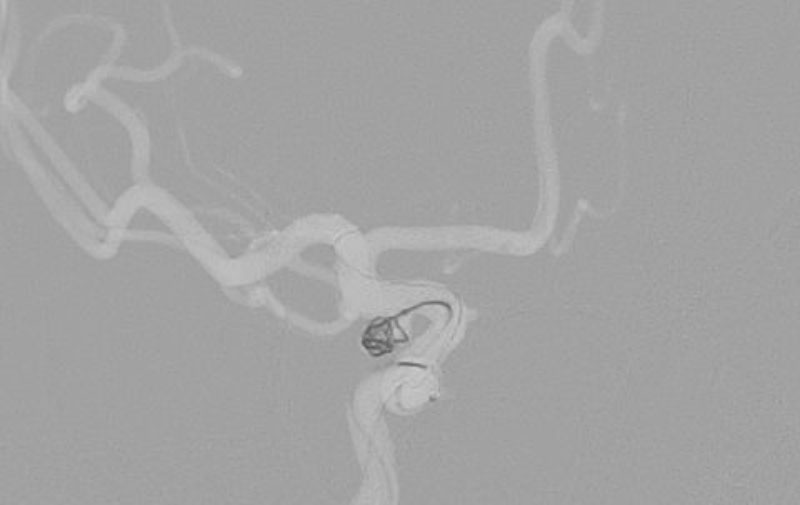

No.1593 手術前

No.1593 手術中

No.1593 手術後

'25年11月

くも膜下出血

右内頚動脈後交通動脈

分岐部動脈瘤破裂

60代

救急外来